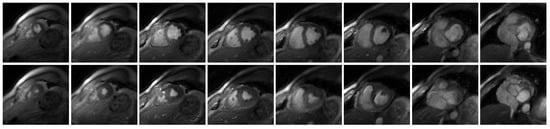

In Figure 4, we showed the visual comparison of the reconstructed free-breathing images and the fully-sampled breath-hold images acquired using the bSSFP sequence. The slices shown in Figure 4 were from Subject #4. Figure 5 was the visual comparison of the reconstructed free-breathing images and the fully-sampled breath-hold images acquired using the FGRE sequence. We reconstructed the whole time series, and we randomly chose a cardiac cycle (from end-systolic to end-diastolic) for comparison with the breath-hold cine.

Figure 5.

Visual comparison of the reconstructed free-breathing images and the fully-sampled breath-hold images acquired using FGRE sequence. For each subject, we acquired fully-sampled breath-hold images for one middle slice using the FGRE sequence. End-systolic and end-diastolic phases from two slices from two subjects are shown in the figure.